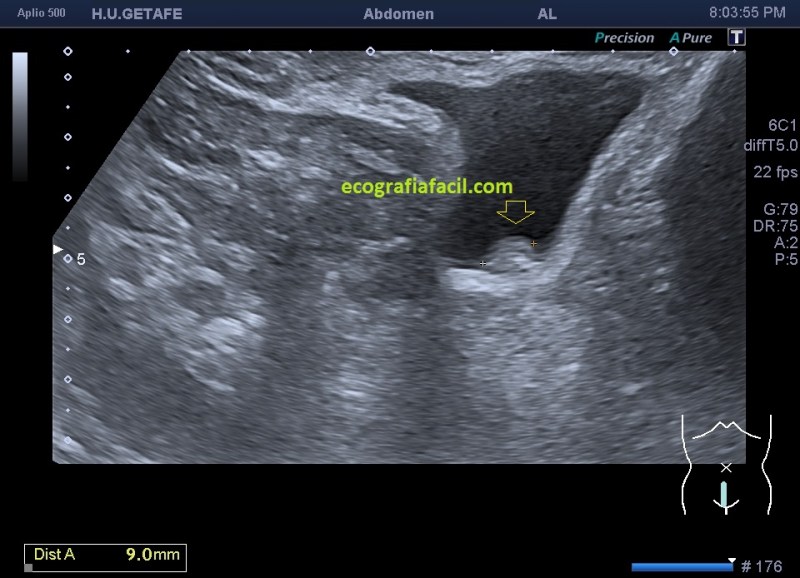

La imagen 2,3,4 y 5 demuestran una lesión de pared vesical, ovalada, hiperecogénica, muy pequeña, con un calcio en su interior (flecha amarilla), pequeña para poder demostrar vascularización, sospecha en el informe de tumor maligno de vejiga, el paciente entra en circuito de neoplasia precoz. A las pocas semanas fue operado, no hizo falta quitarle la vejiga. La detección fue en este caso, vital.

En este tipo de lesiones, si conseguimos demostrar vascularización, es diagnóstico confirmado de Urotelioma.

Observa como cambia todo entre la imagen 1 y 2, marcando la flecha amarilla el mismo lugar y la variación sustancial de como se ve una lesión en una vejiga distendida y en otra que no lo está, ojo que estas situaciones son cotidianas y el paciente puede ser asintomático.